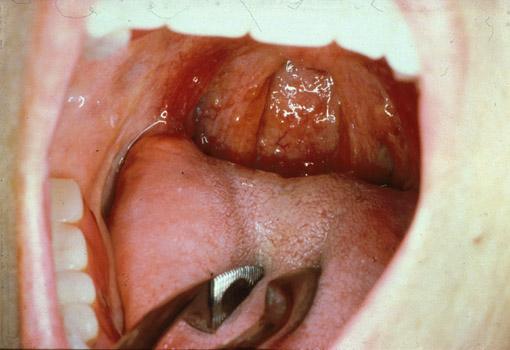

克罗恩(Crohn)病(肠)

在食道、胃、十二指肠伴有微小及细微病变的1例小肠Crohn氏病

炎症性・溃疡性疾患/克罗恩病

部位(按器官分)

切除标本(宏观)